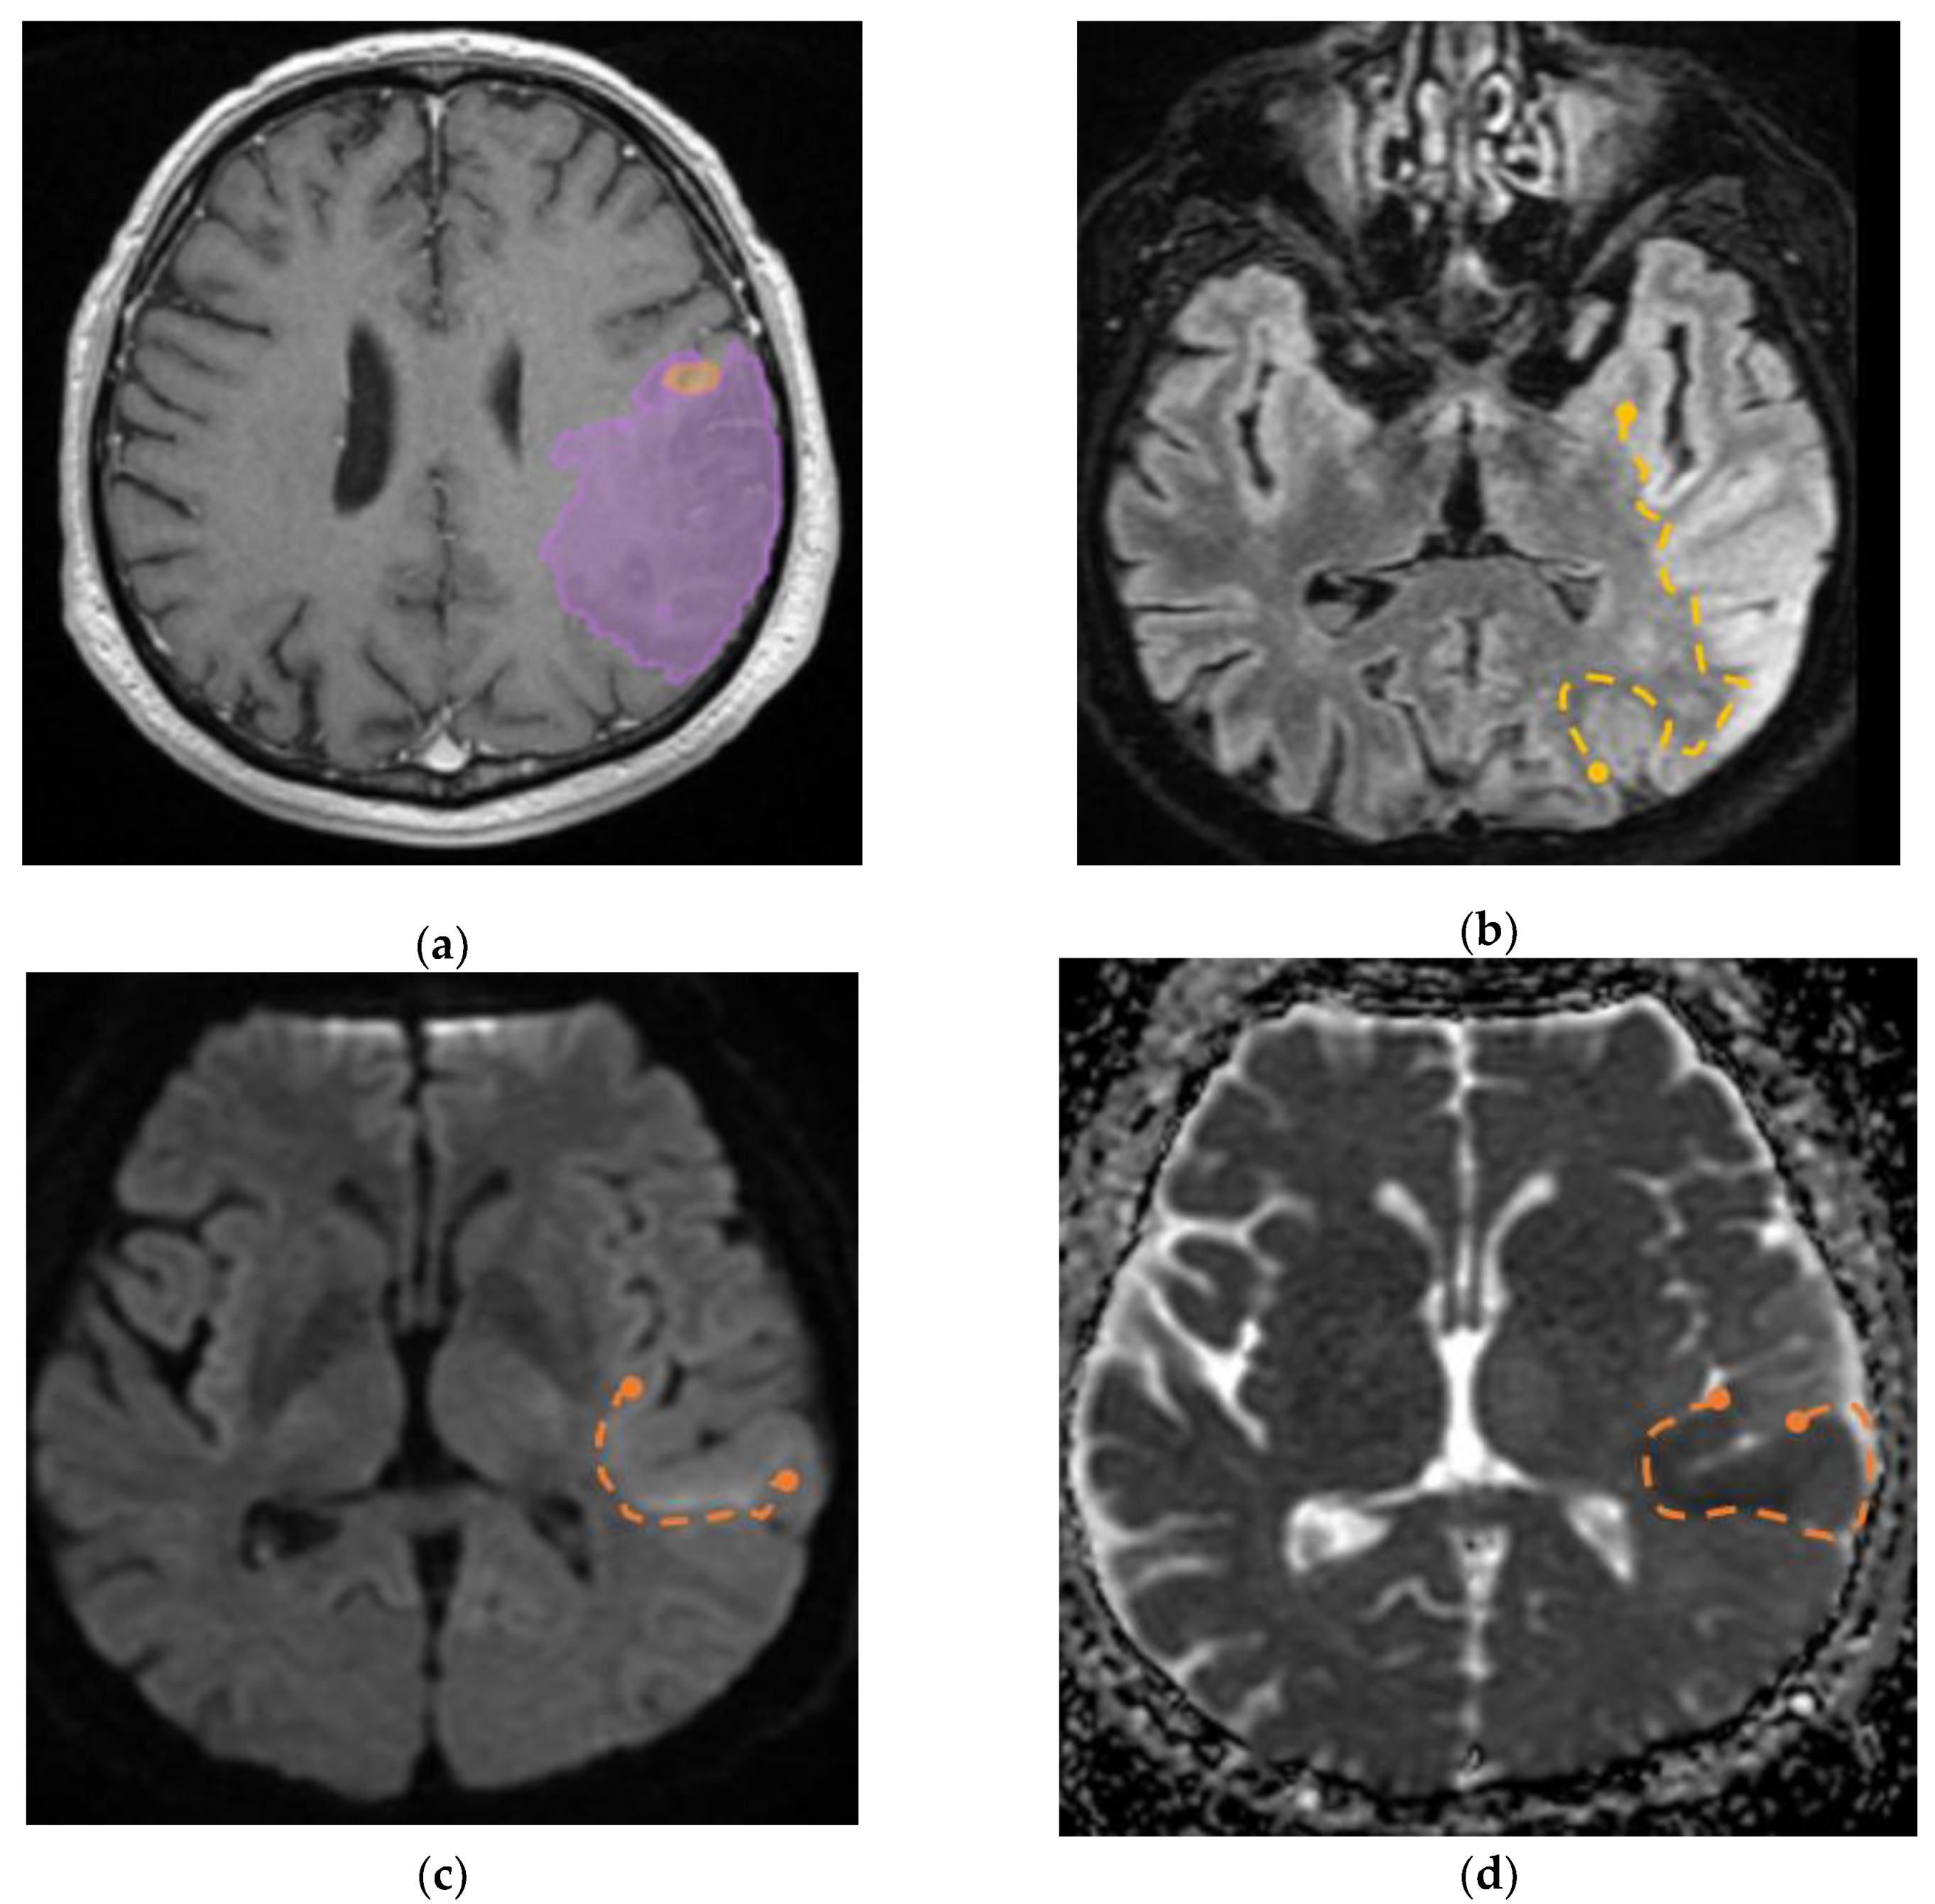

Furthermore, we identified a specific case involving a patient diagnosed with GBM that had visible invasion in the adjacent parenchyma, the aspect on MRI imaging is seen in

Figure 9.

(a) Mdbrain processing of MRI brain acquisition (DICOM) – purple area corresponding to T2W FLAIR hyperintensity; (b) T2W FLAIR, axial plane, manual delimitated (yellow dotted line) hyperintense area corresponding to edema/ parenchymal invasion; (c) DWI, axial plane, discreet hyperintensity in the immediate subcortical area, manually delineated (orange dotted line); (d) ADC map – hypo-intensity corresponding to the DWI hypersignal, suggesting parenchymal invasion, manually delimitated (orange dotted line) (approval was obtained from the Ethics Committee of the University of Medicine and Pharmacy “Grigore T. Popa” Iasi).